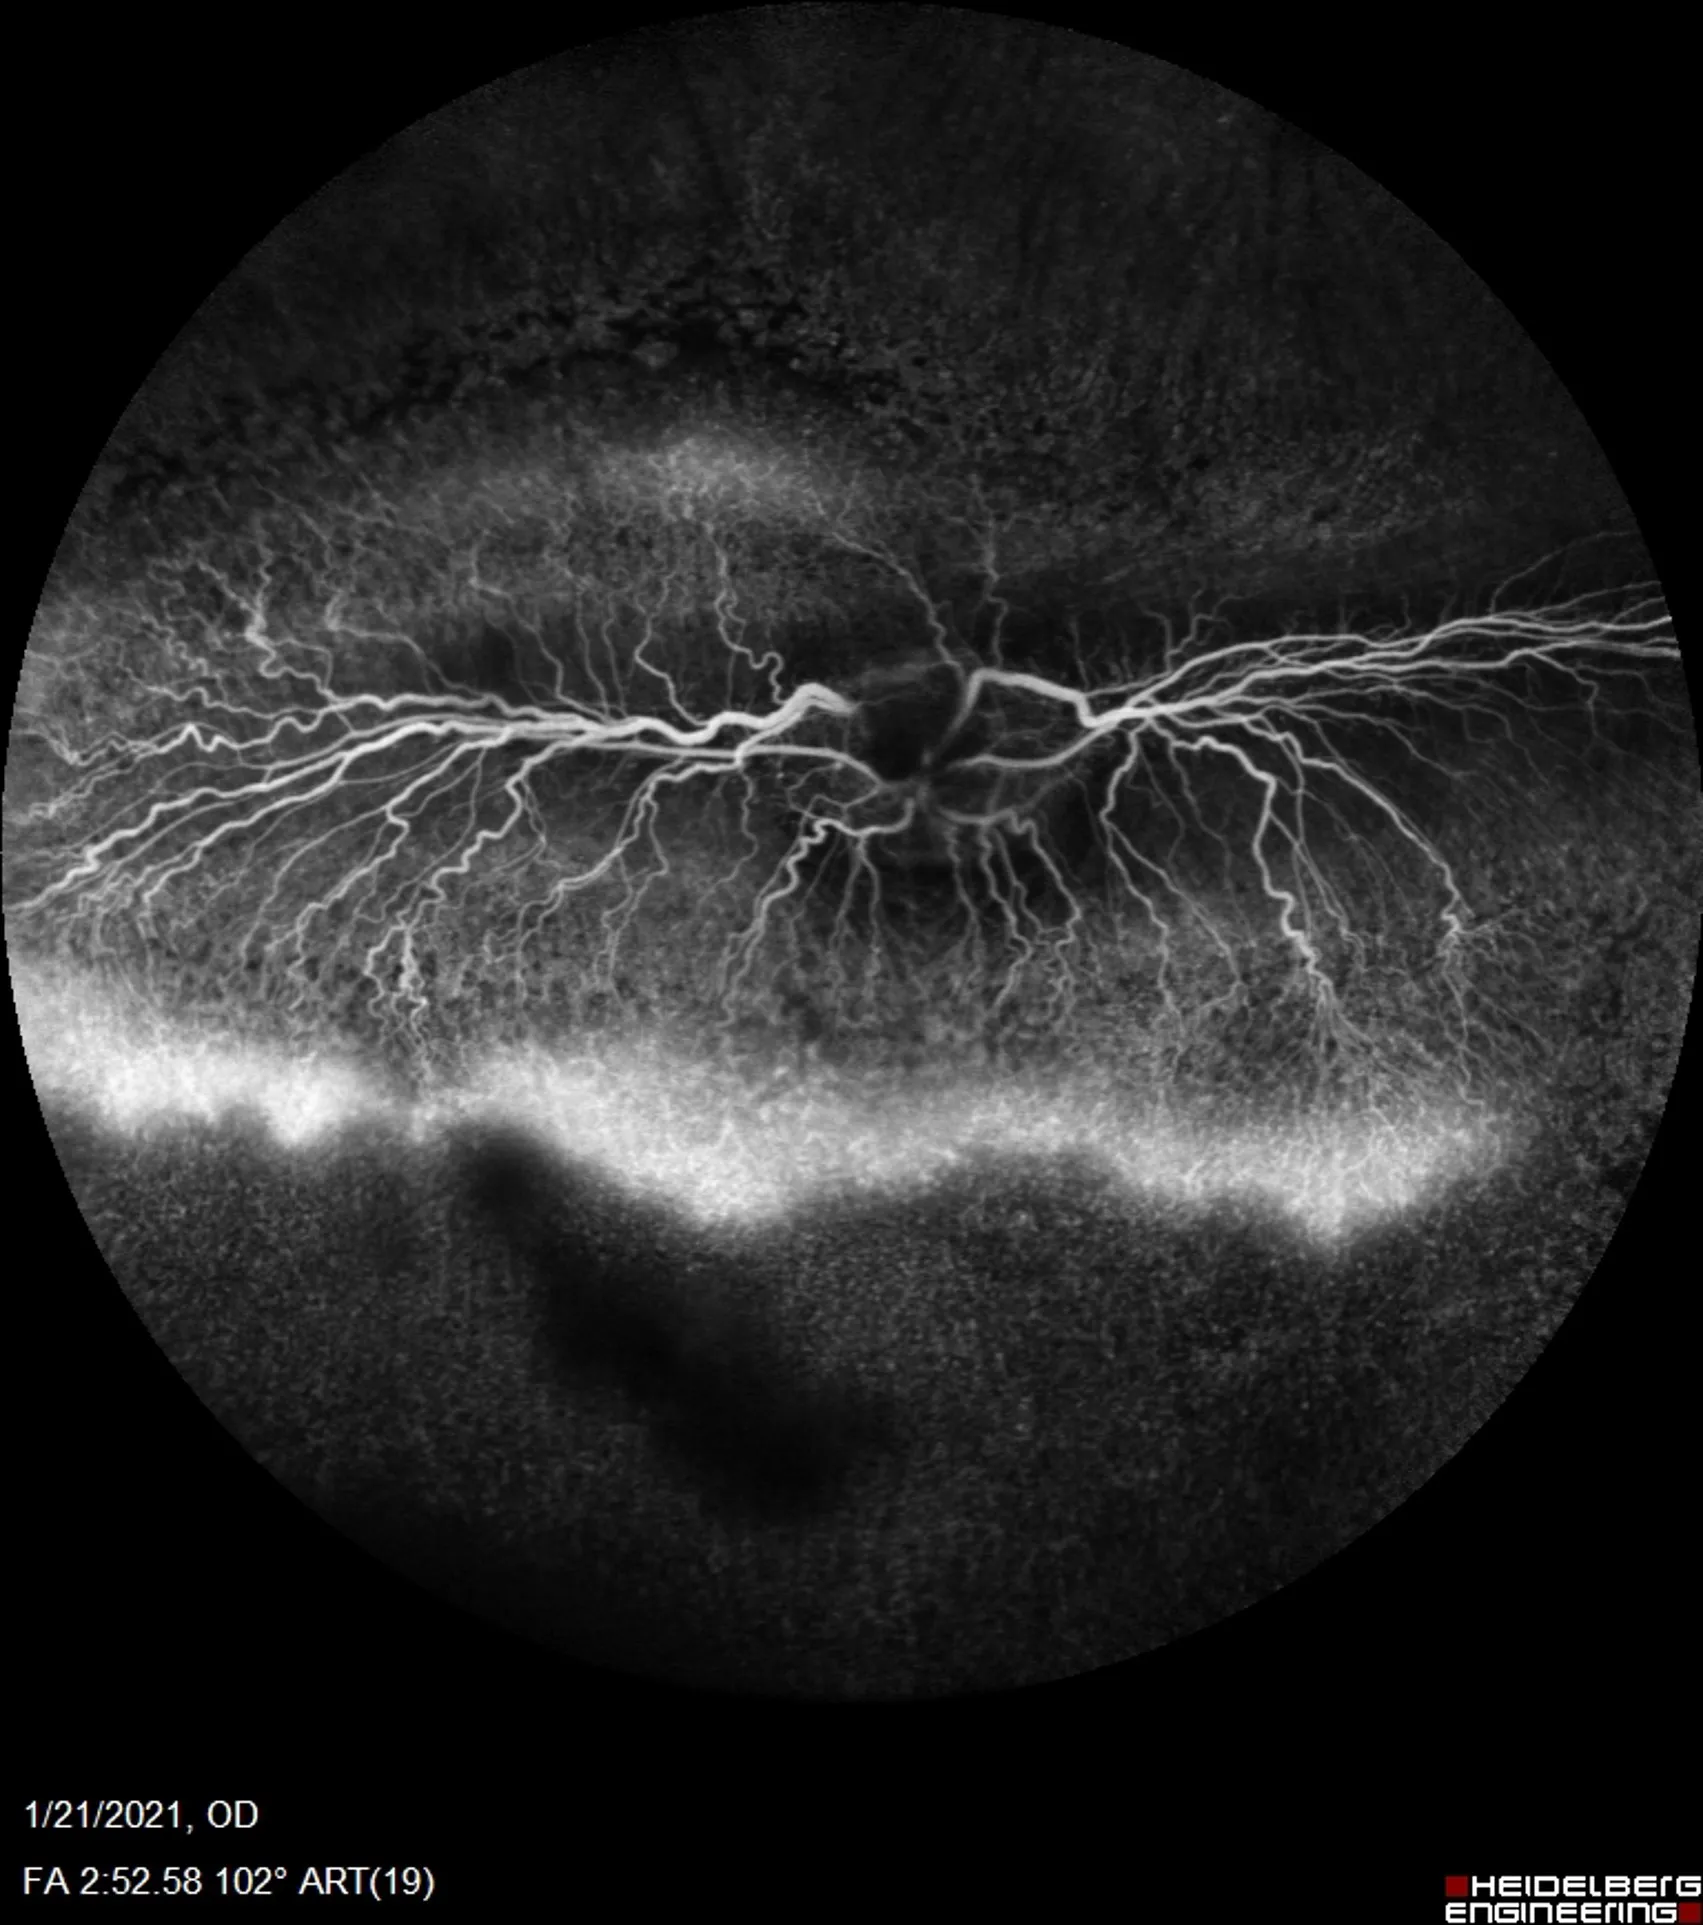

Advances in in vivo imaging, such as fluorescein angiography and optical coherence tomography, enable real-time tracking of disease progression and therapeutic response in the same animals over time, reducing reliance on terminal endpoints.

A qualitative grade of retinal leakage (FA)

Supports longitudinal in vivo imaging

Compatible with advanced imaging techniques (e.g., fluorescein angiography) for noninvasive, time-resolved monitoring of disease, treatment response and relapse.